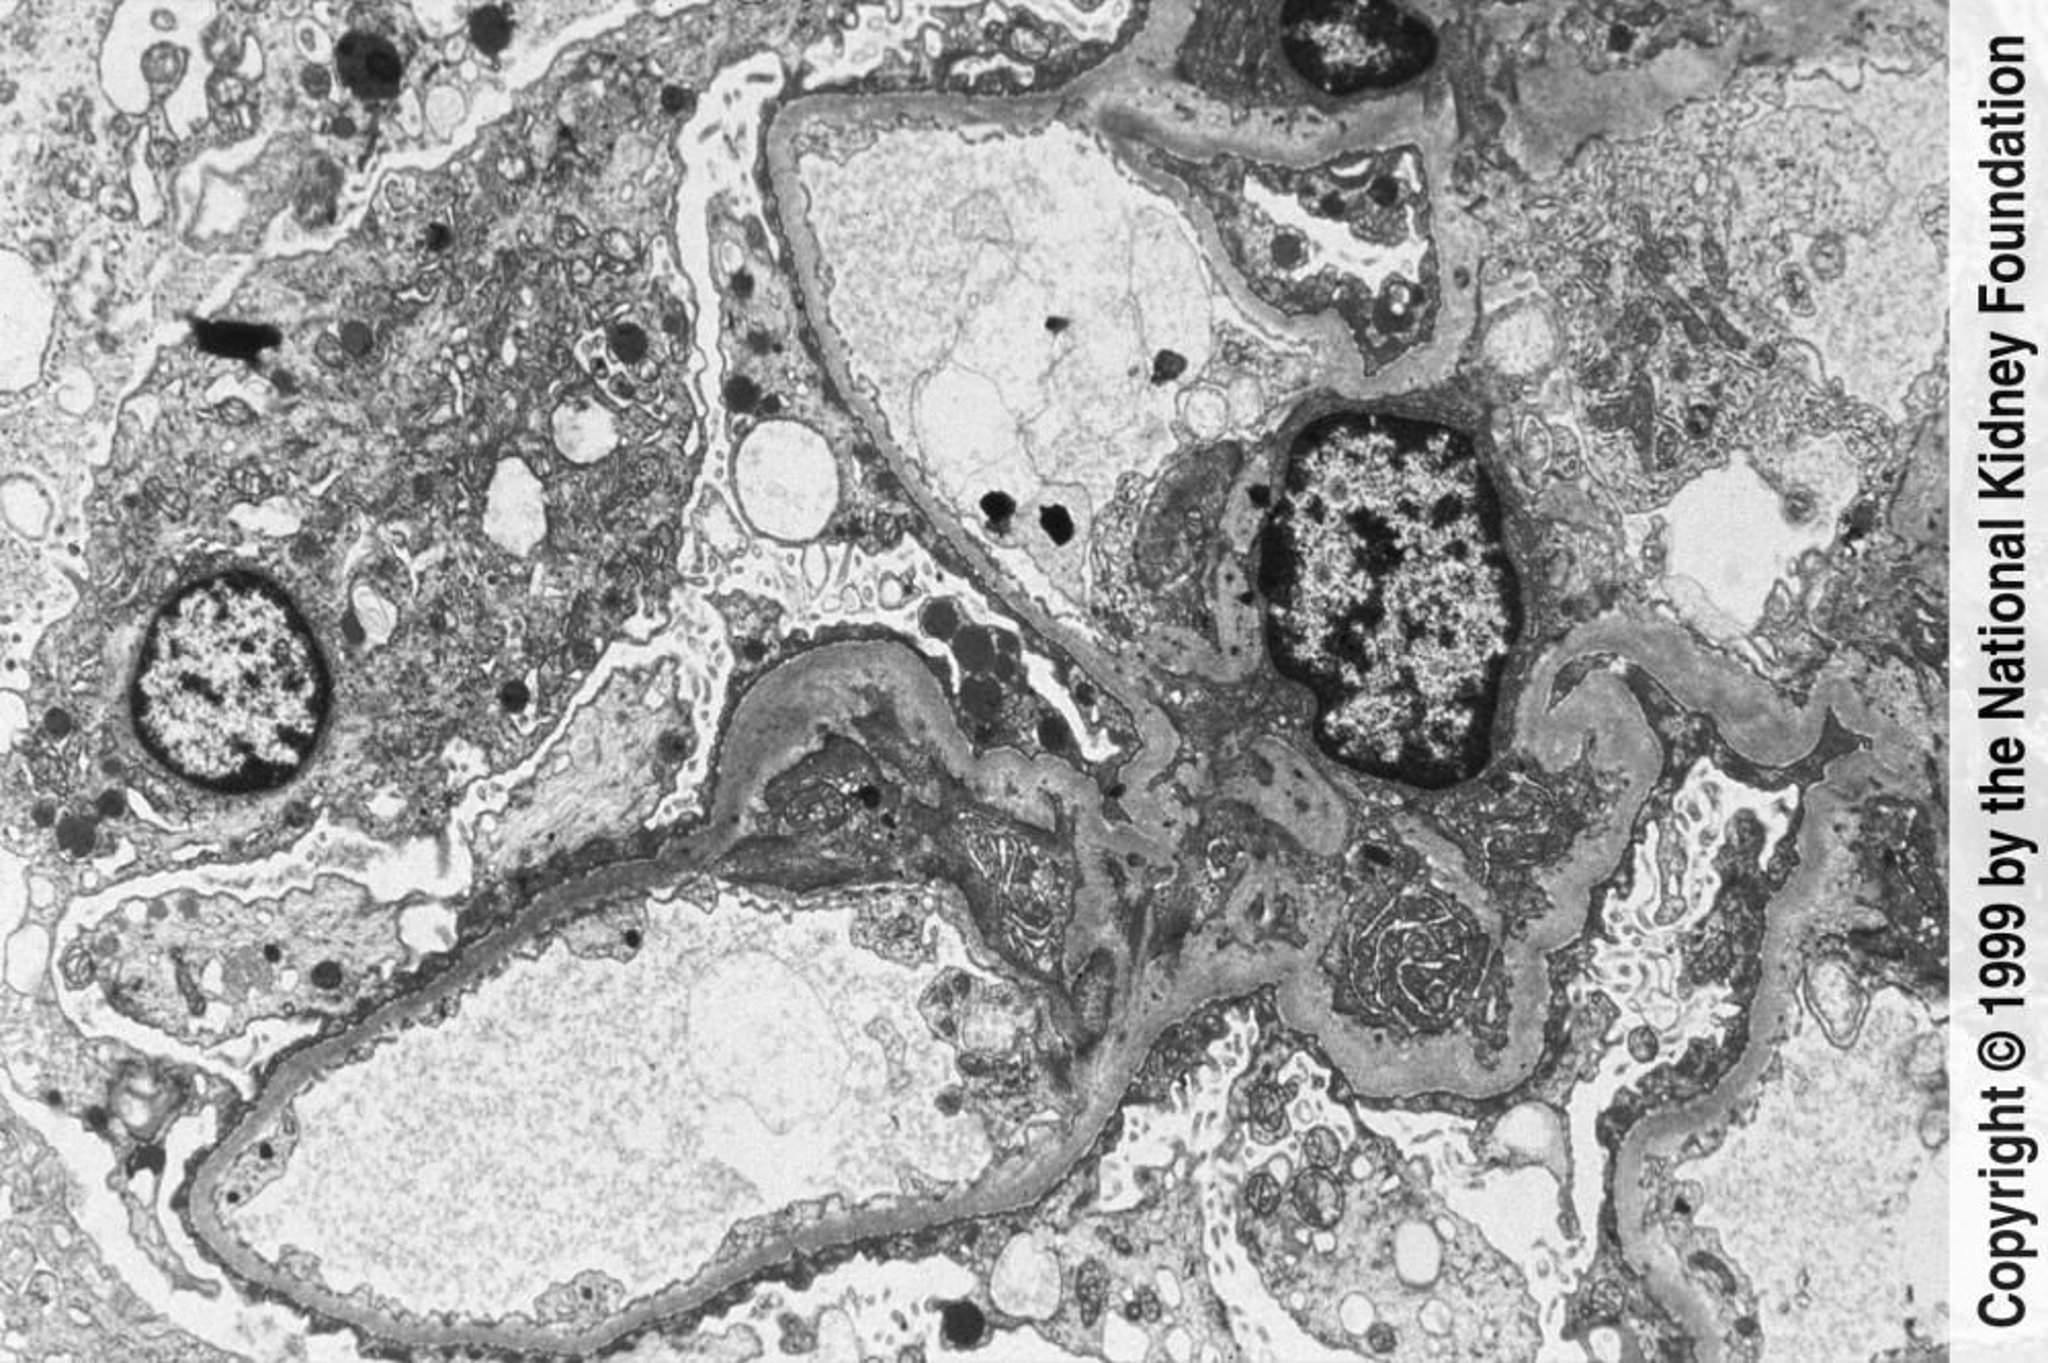

Glomerulosclerosi focale segmentale (appiattimento e scomparsa dei processi podocitari)

Alla microscopia elettronica a trasmissione possono essere osservati un esteso rigonfiamento e scomparsa dei processi podocitari (×3000).

Imagine fornita da Agnes Fogo, MD, and the American Journal of Kidney Diseases' Atlas of Renal Pathology (vedi www.ajkd.org).